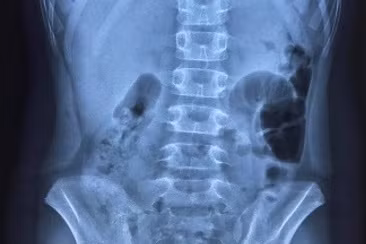

Hình ảnh chụp X-Quang bệnh nhi thể hiện liềm hơi dưới vòm hoành 2 bên, dấu hiệu chẩn đoán thủng tạng rỗng. Ảnh: Bệnh viện Trẻ em Hải Phòng.

Thông tin từ Bệnh viện Trẻ em Hải Phòng cho biết, vừa qua, bệnh viện đã tiếp nhận và xử trí mổ thành công cho 3 bệnh nhi bị thủng tạng rỗng nghi do dùng thuốc sai cách.

Qua test nhanh Covid-19, bệnh nhi D. có kết quả dương tính SARS-CoV-2 nên được chuyển vào khu cấp cứu riêng. Tại đây, qua hồ sơ chuyển viện từ BVĐK Tiên Lãng và thông tin bệnh án đã được Bệnh viện Trẻ em hội chẩn từ xa, kip trực khoa Ngoại của Bệnh viện Trẻ em chẩn đoán bệnh nhi bị thủng tạng rỗng.

Cùng ngày (22/2/2022), một bệnh nhi 5 tuổi mắc Covid-19 (ở An Biên, quận Lê Chân) được đưa vào viện trong tình trạng nôn sốt, đau bụng. Qua kiểm tra, chiếu chụp và thăm khám, kip trực đã chẩn đoán bệnh nhi bị viêm phúc mạc do thủng dạ dày. Khoảng 20 giờ, bệnh nhi được tiến hành phẫu thuật.

Bac sĩ khuyến cáo, việc 2 bệnh nhi bị thủng tạng rỗng, rất có thể tác nhân gây ra do dùng thuốc không đúng cách. Vì vậy, phụ huynh không nên tự ý sử dụng các loại thuốc chống viêm khi chưa có chỉ định của bác sĩ.

Theo lưu ý từ chuyên gia y tế, bệnh nhân bị thủng dạ dày phải được cấp cứu khẩn cấp, đòi hỏi chẩn đoán và xử trí kịp thời bởi có thể dẫn đến nhiều biến chứng nguy hiểm, thậm chí nguy hiểm tính mạng.

Thủng dạ dày ít gặp ở trẻ em, dễ bị chẩn đoán nhầm với bệnh lý ngoại khoa cấp tính khác như viêm ruột thừa, tắc ruột.